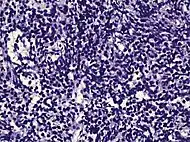

Intraductal carcinoma of the prostate with an infiltrative growth pattern may be morphologically difficult to distinguish from invasive cancer. One focus shows comedonecrosis (arrow), morphologically suggesting Gleason pattern 5 invasive carcinoma (a haematoxylin and eosin, b CK5/6)[19]